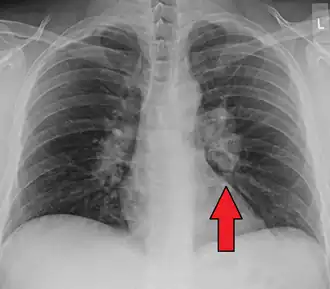

![]() | |

Chest X-ray showing the typical nodularity of sarcoidosis, predominantly in the hila of the lungs. | |

Chest radiograph changes are divided into four stages:[104]

- bihilar lymphadenopathy

- bihilar lymphadenopathy and reticulonodular infiltrates

- bilateral pulmonary infiltrates

- fibrocystic sarcoidosis typically with upward hilar retraction, cystic and bullous changes

Although people with stage 1 radiographs tend to have the acute or subacute, reversible form of the disease, those with stages 2 and 3 often have the chronic, progressive disease; these patterns do not represent consecutive "stages" of sarcoidosis. Thus, except for epidemiologic purposes, this categorization is mostly of historic interest.[28]

-

Hilar adenopathy especially on the person's left (AP CXR)

Hilar adenopathy especially on the person's left (lateral CXR)

Hilar adenopathy especially on the person's left (coronal CT)

Hilar adenopathy especially on the person's left (transverse CT)